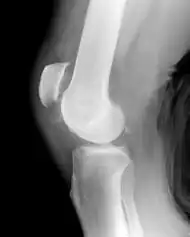

| Patellar tendon rupture showing a great distance between the tibial tuberosity and the bottom of the knee cap. Arrow marks this enlarged space. | |

Patellar tendon rupture can usually be diagnosed by physical examination. The most common signs are: tenderness, the tendon's loss of tone, loss of ability to raise the straight leg and observation of the high-riding patella. Radiographically, patella alta can be detected using the Insall and Salvati method when the patella is shorter than its tendon. Partial tears may be visualized using MRI scans.[4]